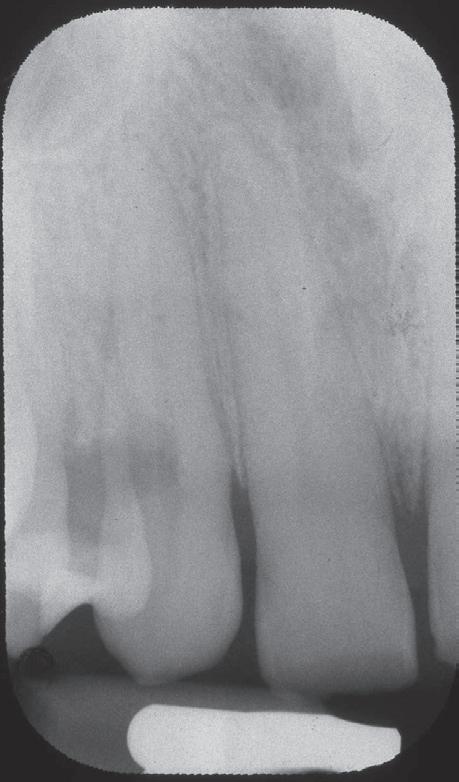

Een 67-jarige patiënt (ASA I) wordt doorverwezen voor een endodontische behandeling op tand 34 om-

wille van necrose en de daaruit volgende symptomatische apicale parodontitis. Na klinisch onderzoek kan een buccale cervicale klasse V composietrestauratie met randlekkage en secundaire cariës weerhouden worden. De tand is intact op het occlusaal oppervlak (afbeelding 1a, b, c). Pre-operatieve peri-apicale radiografie toont een apicaal letsel met een normaal verloop van het wortelkanaal (afbeelding 2a). Eén jaar follow-up toont volledige apicale genezing aan en klinisch zijn er geen tekenen van secundaire cariës.

Na verdoven en plaatsen van rubberdam-isolatie, is de eerste stap het maken van de openingscaviteit, waarbij er in deze situatie twee mogelijkheden zijn:

1.Een klassieke toegang doorheen het gave occlusale vlak samen met het behandelen van de buccale composiet restauratie en cariës (voordeel: straight line access. Nadeel: twee verzwakkingen).

2.Verwijderen van de buccale restauratie en cariës en behoud van het occlusale vlak. (Voordeel: gebruik-

maken van een reeds aanwezige verzwakking en behoud van gaaf tandweefsel. Nadeel: meer geanguleerde toegang naar het wortelkanaal).

De keuze om gebruik te maken van de reeds aanwezige restauratie ligt in dit geval voor de hand (Restorative and Caries-Driven access cavity) (afbeelding 3a), maar hierbij dient rekening gehouden te worden met de locatie van het kanaal ten opzichte van het buccale oppervlak (afbeelding 4a).

Voor verdere preparatie van het wortelkanaal is het belangrijk om een goed referentiepunt te krijgen, wat niet altijd even éénvoudig blijkt te zijn bij dit soort openingscaviteiten. Een handig hulpmiddel kan zijn om een bolletje composiet of ander licht uithardend, achteraf makkelijk te verwijderen, kunsthars aan te brengen als referentiepunt tijdens de preparatie en obturatie (afbeelding 5a, b, c), ofwel door gebruik te maken van een ingebouwd apex locator in de preparatie-motor.14 Na volledige mechanische prepara-

tie met dead-soft rotaries – om breuk te voorkomen bij de geanguleerde toegang – wordt met gehaakte sondes en ultrasone tips het meer coronaal gelegen deel van de pulpakamer gereinigd. Na activatie van het spoelmiddel (afbeelding 6a, b) kan het element worden gevuld met guttapercha en een sealer naar keuze (afbeelding 7a, b, c). Vervolgens wordt de tand hersteld met een composietrestauratie (afbeelding 8a, b, c). Eén jaar follow-up toont volledige apicale genezing aan en klinisch zijn er geen tekenen van secundaire cariës (afbeelding 9a).